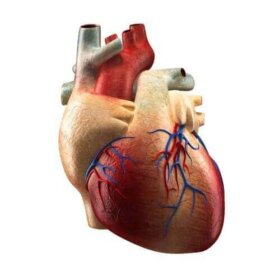

심장은 생명을 유지하기 위한 필수 기관의 하나이며 순환계의 주인공이라고 할 수 있다. 심장은 산화된 피를 몸 전체로 펌프질하는 역할을 한다. 대부분 사람은 심장이 얼마나 중요한지 알고 있지만, 심장의 구성 요소와 기능에 대해 포괄적으로 이해하고 있는 사람은 거의 없다. 심장에는 다양한…